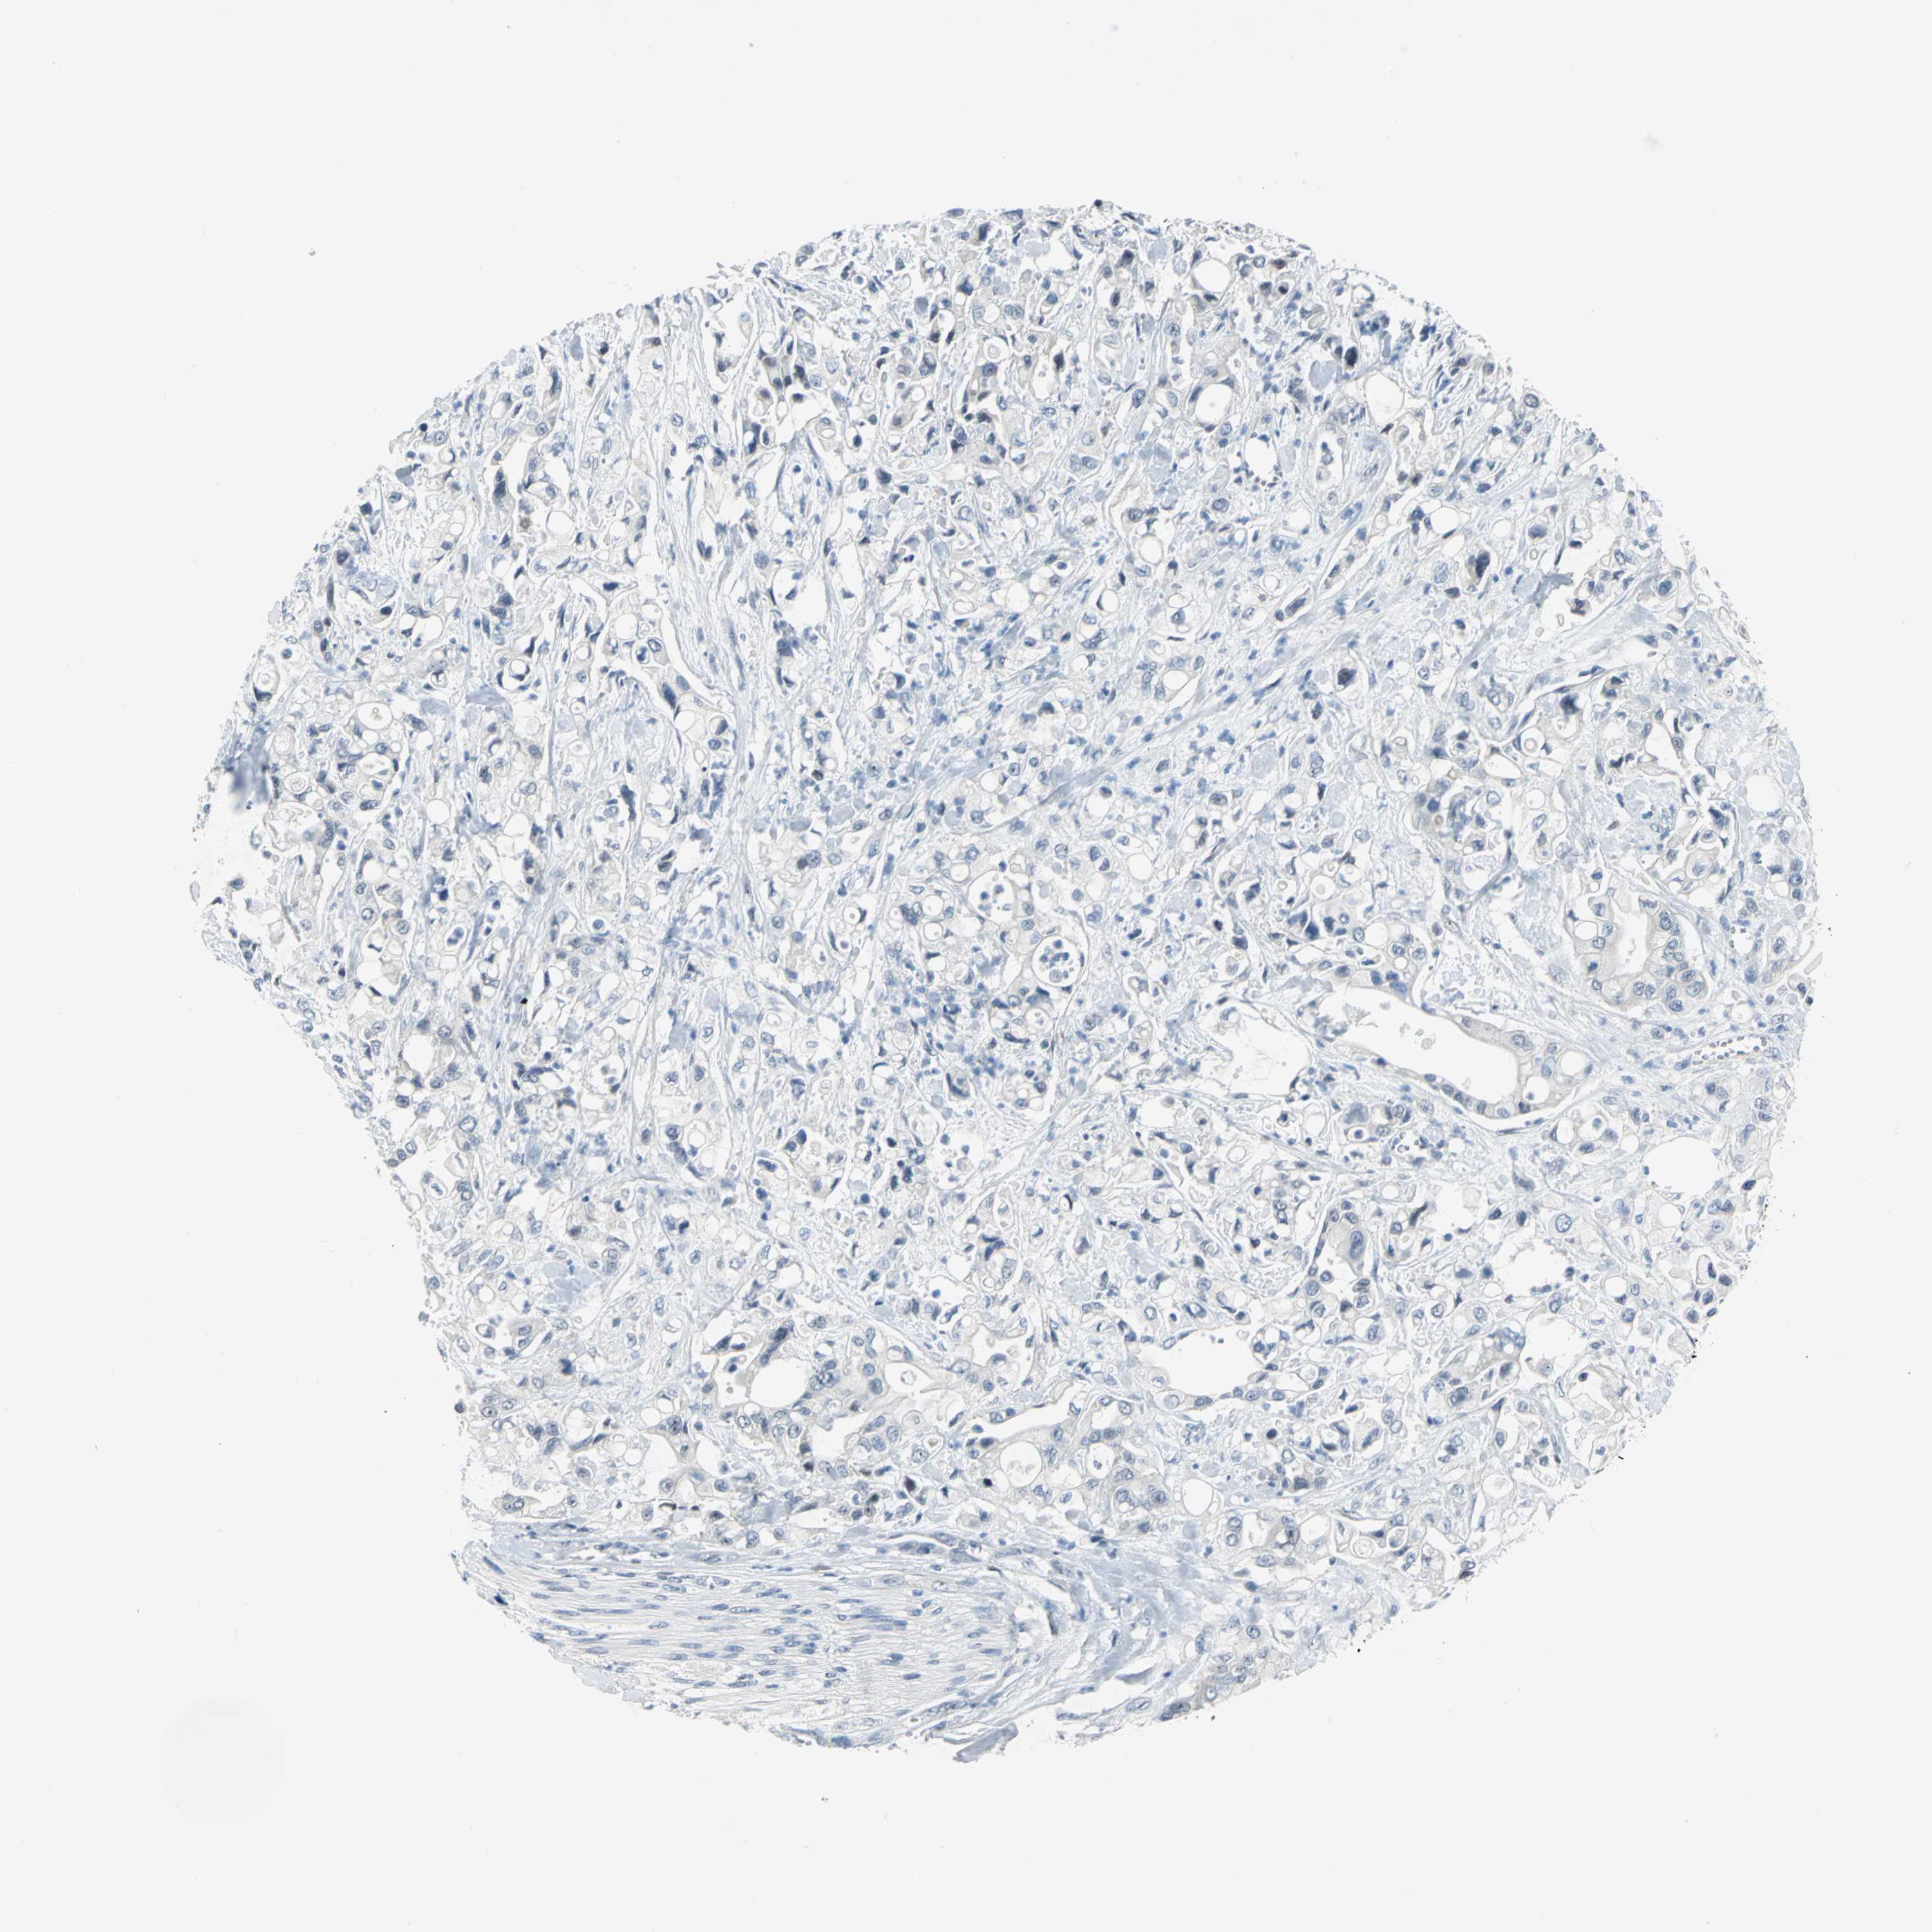

PANCREATIC CANCER - Protein expressioni

A mouse-over function shows sample information and annotation data. Click on an image to view it in a full screen mode. Samples can be filtered based on level of antibody staining by selecting one or several of the following categories: high, medium, low and not detected. The assay and annotation is described here.

Note that samples used for immunohistochemistry by the Human Protein Atlas do not correspond to samples in the TCGA dataset.

Antibody stainingi

Antibody staining in the annotated cell types in the current human tissue is reported as not detected, low, medium, or high, based on conventional immunohistochemistry profiling in selected tissues. This score is based on the combination of the staining intensity and fraction of stained cells.

Each image is clickable and will lead to virtual microscopy that enables deeper exploration of all samples and also displays staining intensity scores, fraction scores and subcellular localization as well as patient and tissue information for each sample.

Antibody HPA005466

Staining

High

Medium

Low

Not detected

Intensity

Strong

Moderate

Weak

Negative

Quantity

>75%

75%-25%

<25%

None

Location

Nuclear

Cytoplasmic/membranous

Cytoplasmic/membranous,nuclear

Adenocarcinoma, NOS

Adenocarcinoma, metastatic, NOS